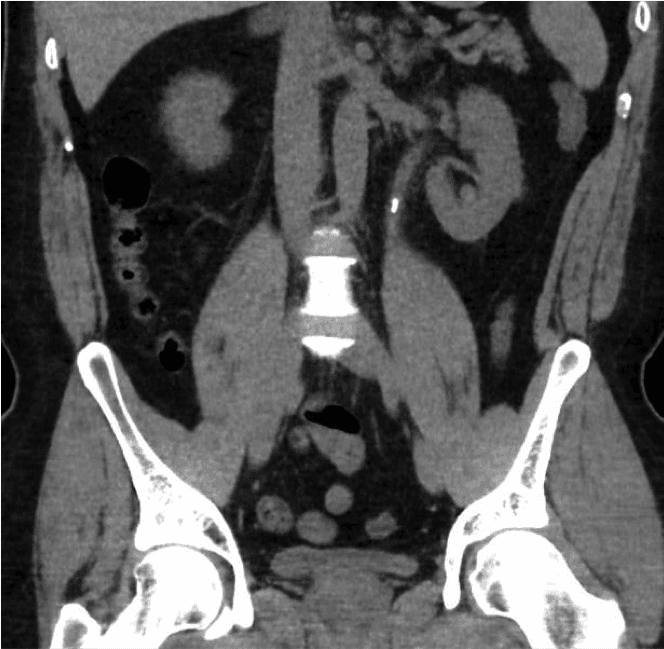

首先會進行尿液試紙檢查,檢查尿液中是否有帶血,並排除泌尿道感染。之後也會進行腎功能和血鈣檢測。結石的最終診斷方法是腹部普通CT掃描(腎臟輸尿管膀胱區CT掃描,簡稱CT KUB)。此掃描可以顯示結石的大小和位置,有助於制定治療方案。